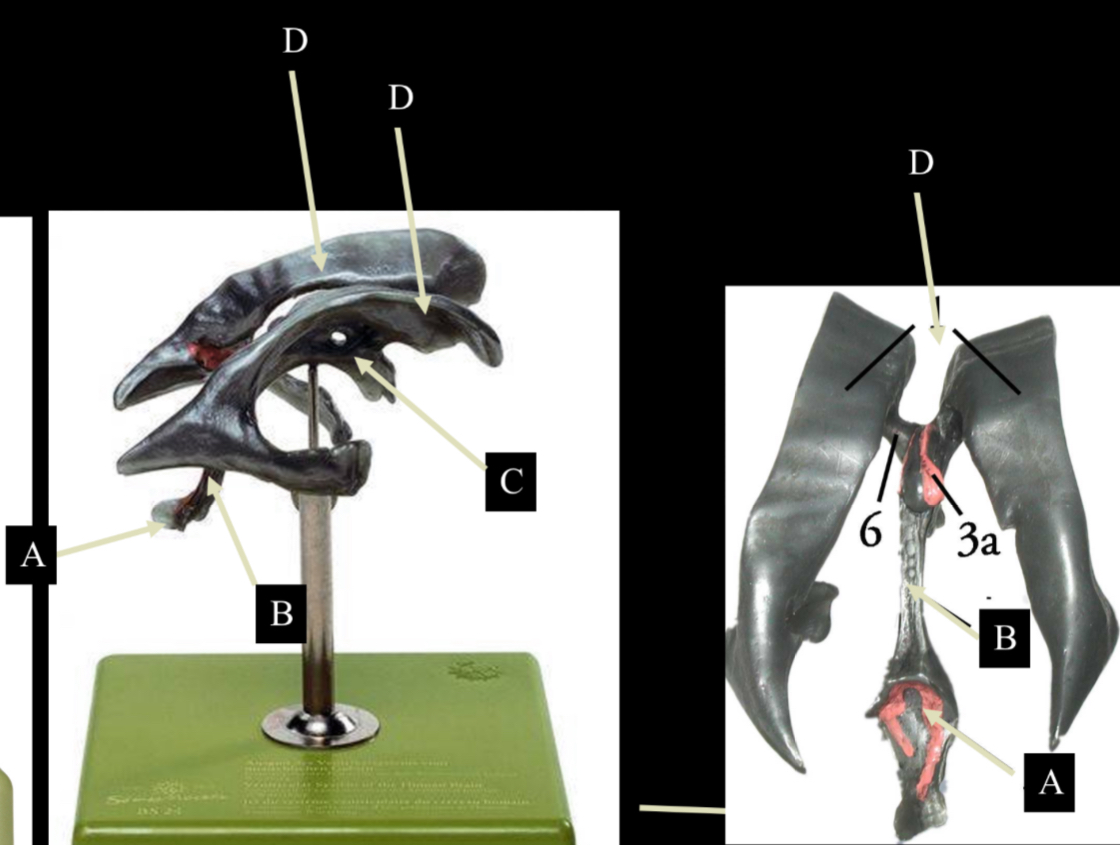

What is D?

lateral ventricle

Imagine thin membrane separating the 2 lateral ventricles

septum pellucidum

What is C?

3rd ventricle

What is B?

cerebral aqueduct

What is A?

4th ventricle

What is below A at the very end?

central canal (spinal cord)